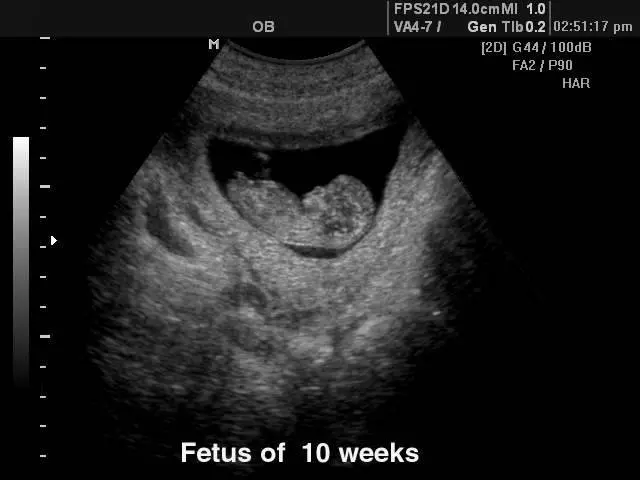

V naši ambulanti se vedno trudimo imeti čimbolj strokoven pristop. To lahko dosežemo le z nenehnim izobraževanjem in spremljanjem razvoja medicinskih postopkov doma ter v tujini. Tako smo se med drugim specializirali za različne preglede, kot je nuhalna svetlina Ptuj.